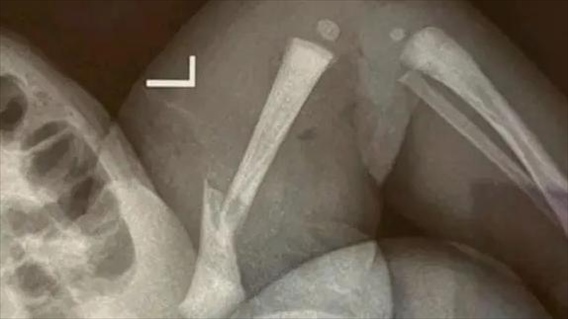

·江蘇靖江新生兒骨折家長質疑系醫(yī)療事故,靖江市人民醫(yī)院:手法不熟導致。